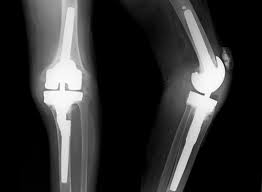

무릎 인공관절 수술, 왜 필요한가요?

무릎관절은 체중을 가장 많이 지탱하는 관절입니다. 나이가 들수록 연골은 점차 마모되고, 충격을 흡수하는 능력도 감소합니다. 이로 인해 통증, 뻣뻣함, 운동 제한이 생기며, 이런 증상이 악화되면 인공관절 수술이 필요해집니다.

퇴행성 관절염 외에도 류마티스 관절염이나 외상 후 관절 손상이 심각할 경우 수술이 권유되며, 수술을 통해 환자는 통증 없이 보행이 가능해지고 일상생활로 복귀할 수 있게 됩니다.